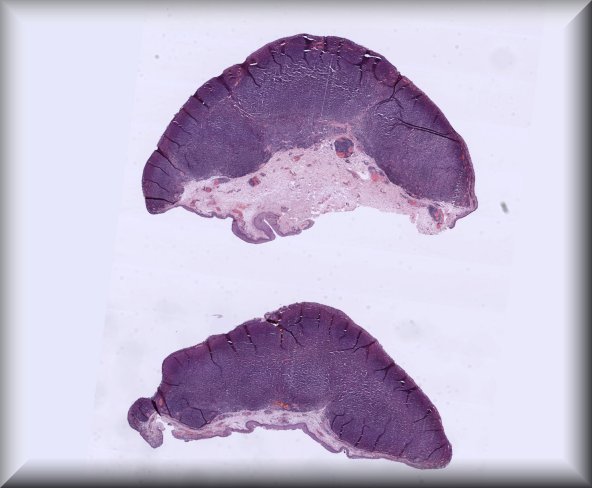

Jolique van Ipenburg (Nijmegen): A thirteen year old girl presents with two conjunctival lesions. The patient reported a traumatic event 2 years earlier, where after she noticed these conjunctival lesions 1 ½ year ago. These lesions seem to become darker over time and people are making remarksfrequently. Clinical examination reveals 2 heavily pigmented mobile highly vascularized lesions located at the bulbar conjunctiva. These lesions do not bleed and are painless. Vision is not impaired. The lesions were excised for both diagnostic and therapeutic reasons. |

||